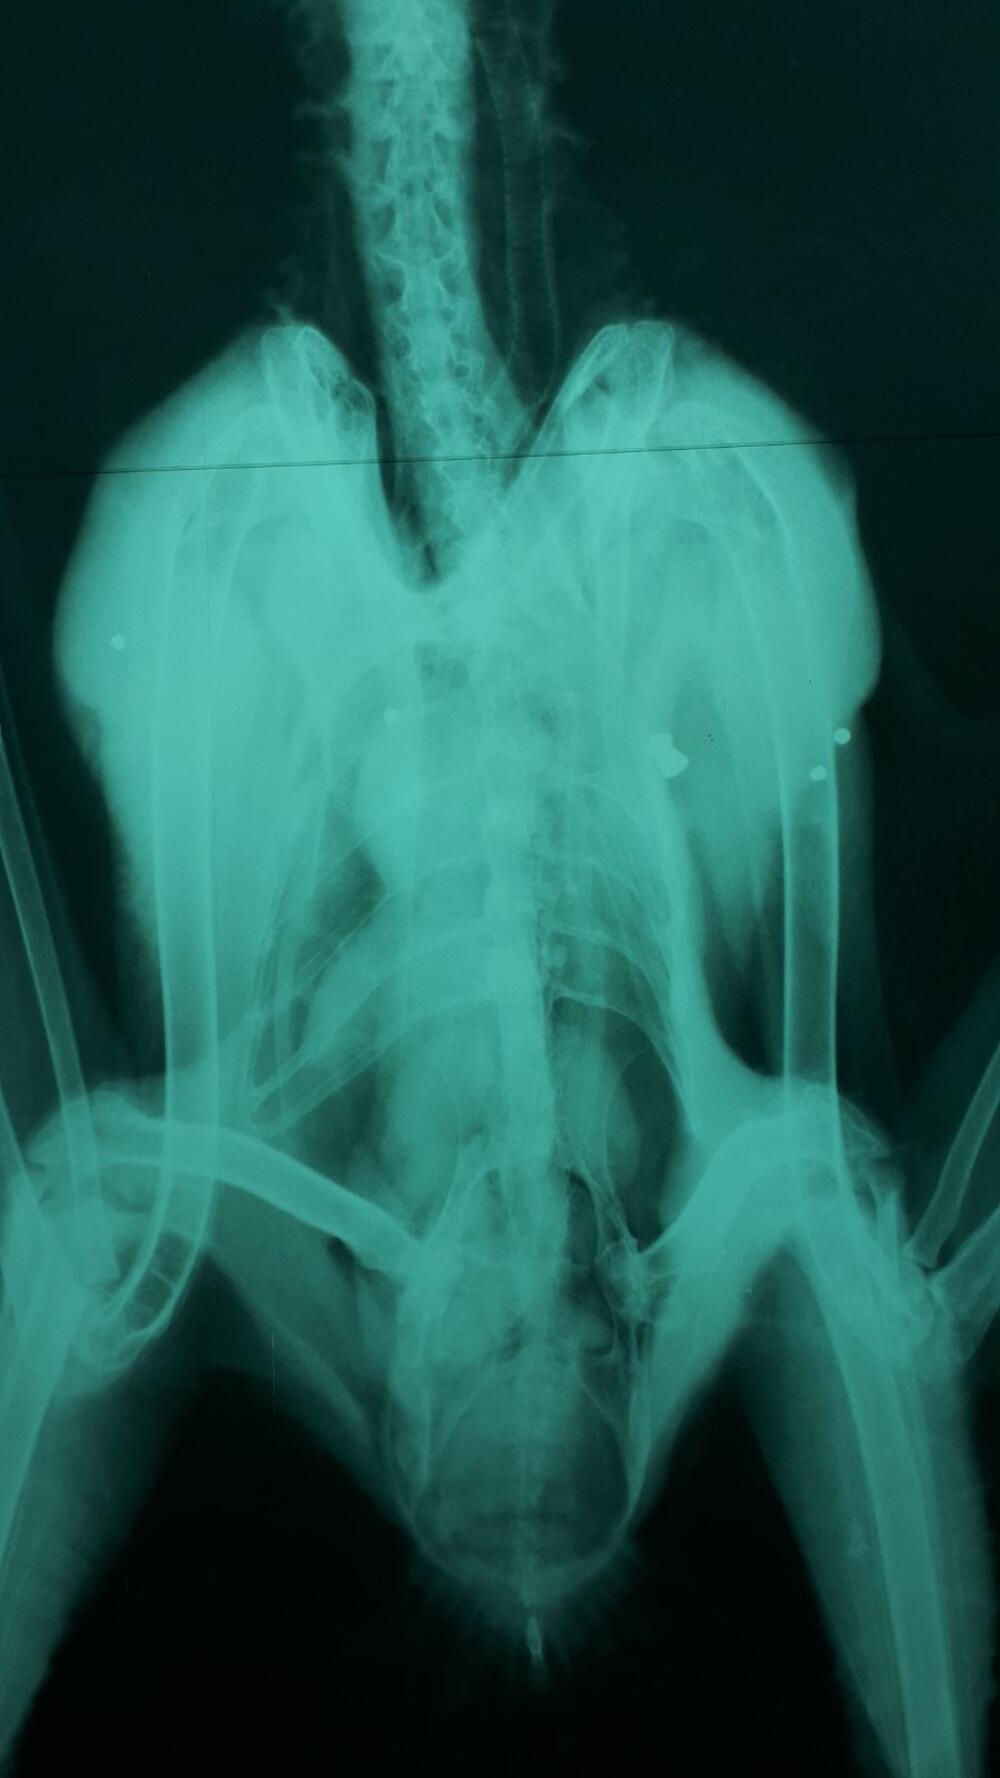

“Sovu smo našli u veoma lošem stanju, dok je CT snimak pokazao tragove balina. Ptica je dugo bila u mukama i imunitet joj je oslabio usljed posljedica trovanja olovom, tako da joj nažalost nije bilo spasa”, kazali su iz te organizacije.

Dodali su da je ptica pucana u više navrata.

“Što dokazuje snimak na kojem se vide tragovi dvije vrste oružja, najverovatnije vazdušne puške i sačmarice. Velika ušara je zakonom zaštićena vrsta i ubijenje je strogo zabranjenjo, te je počinjeno krivično djelo - krivolov”, saopštili su iz CZIP-a, dodajući da je u proteklih nekoliko godina, ta značajna vrsta, osim krivolova, bila žrtva trovanja i elektrokucije.

Snimak pokazuje tragove dvije vrste oružja

Snimak pokazuje tragove dvije vrste oružjafoto: CZIP